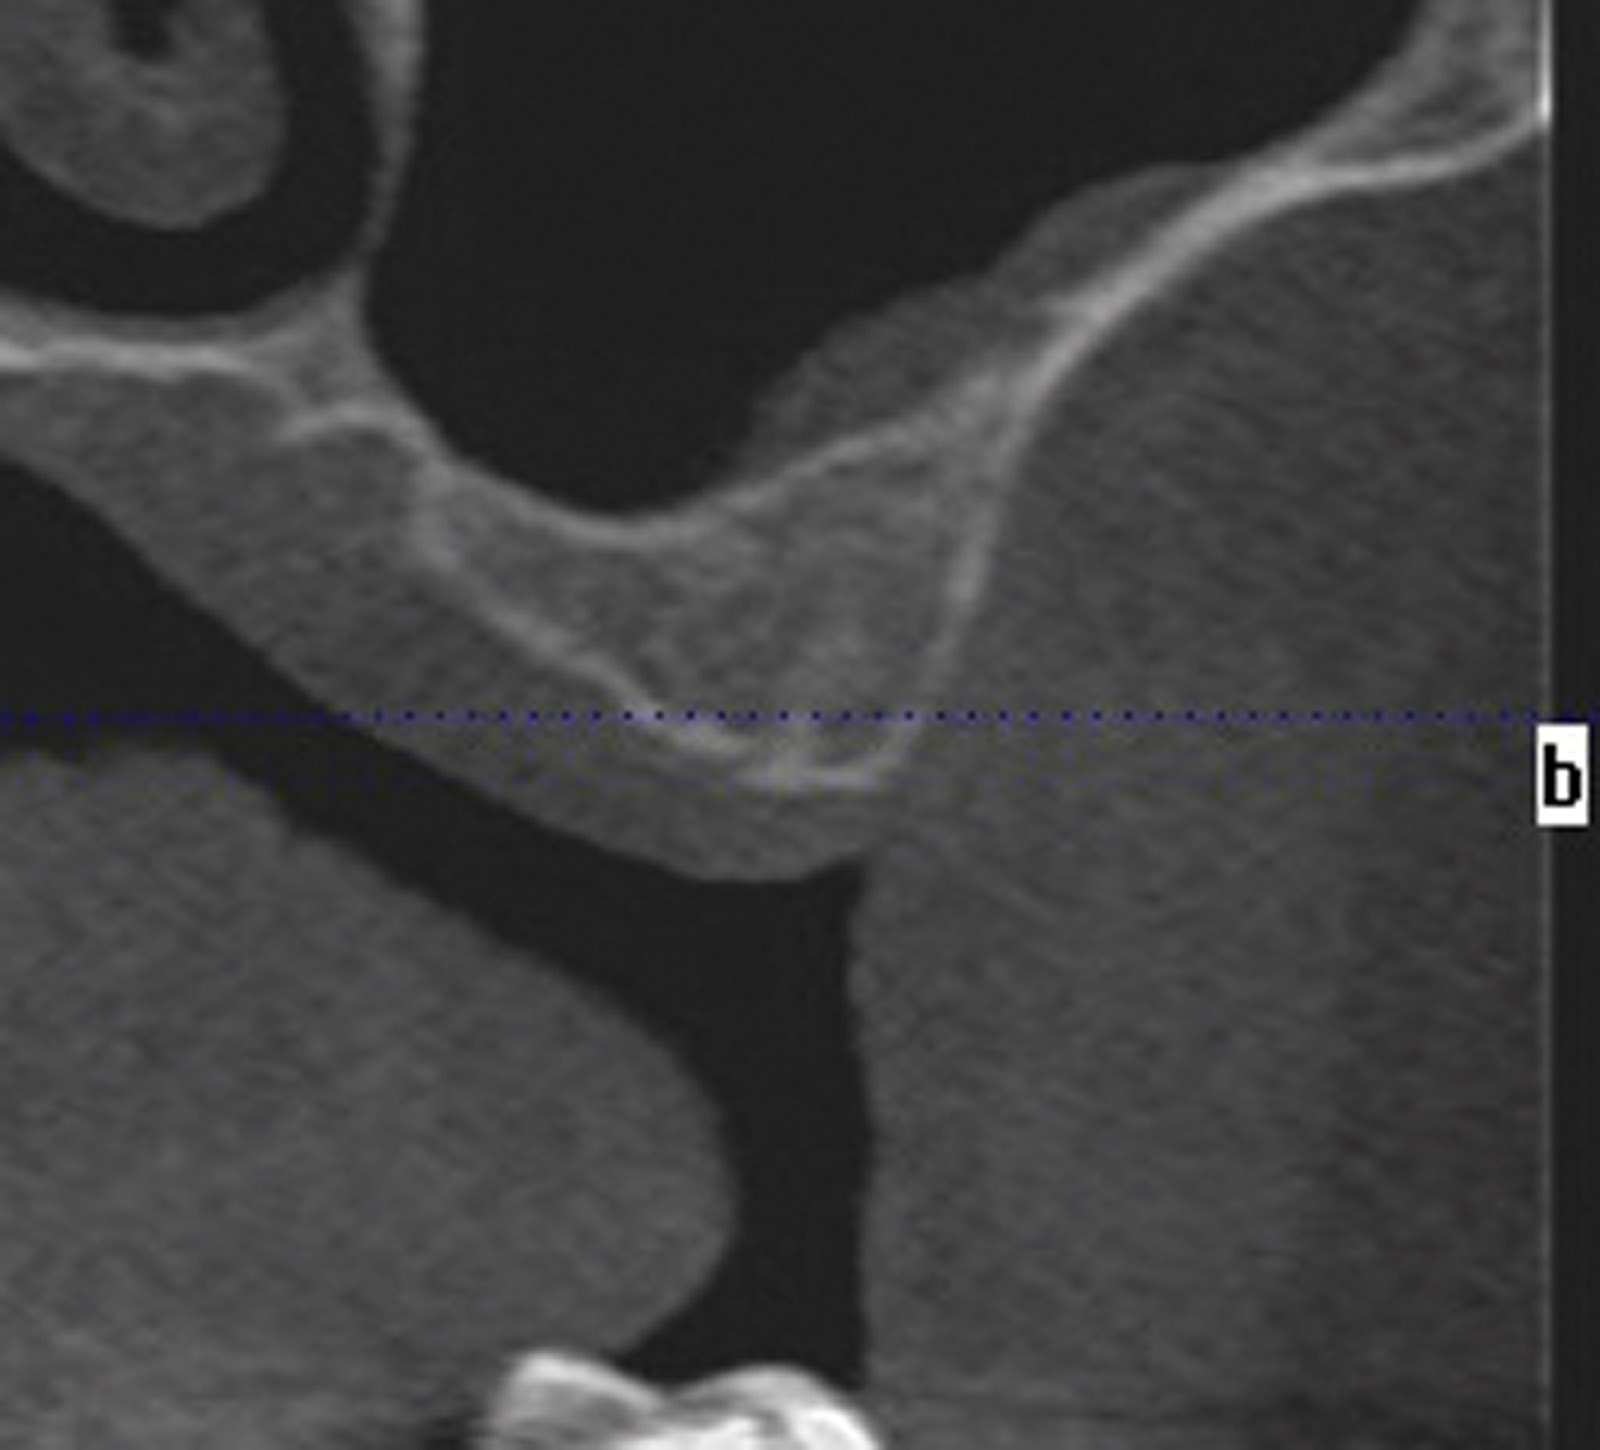

A CBCT scan of the upper jaw was taken to accurately assess the anatomy of the maxilla, the trajectory of the alveolar ridges and to ascertain if immediate implant placement was going to be possible (Figures 4). The scan confirmed adequate bone volume in the anterior maxilla, with good bone height beyond the apices of the failing teeth and intact labial alveolar plates, the density of the trabecular bone was adequate to allow for very good initial primary stability for the immediate placement and loading of the implants. The CBCT scan also confirmed inadequate bone volume beneath the maxillary sinuses (Figure 5).